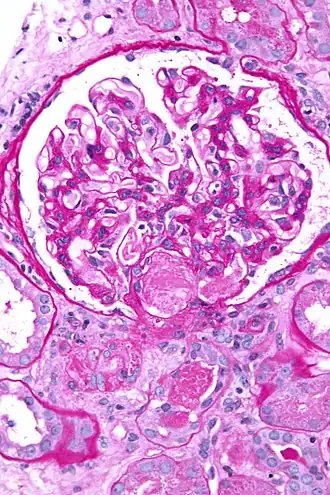

La coagulation intravasculaire disséminée (CIVD), aussi appelée syndrome de défibrination ou coagulopathie de consommation, est une activation pathologique de la coagulation (formation de caillots sanguins). Elle apparaît dans de nombreuses situations pathologiques quand de petits caillots se forment dans les vaisseaux sanguins de tout l'organisme[1]. Ces caillots consomment les facteurs de coagulation. La coagulation normale est ainsi empêchée et des hémorragies (saignements) anormales apparaissent sur la peau (notamment aux sites de prélèvements sanguins), le tube digestif, le tractus respiratoire et les cicatrices chirurgicales. Les petits caillots perturbent aussi le flux sanguin vers les organes (comme les reins) et entraînent une perturbation de leur fonctionnement[2].

- phénomènes thrombotiques : oblitération des petits vaisseaux ;

- des manifestations thrombotiques : thromboses veineuses profondes, infarctus viscéraux, purpura nécrotique, gangrènes distales ;